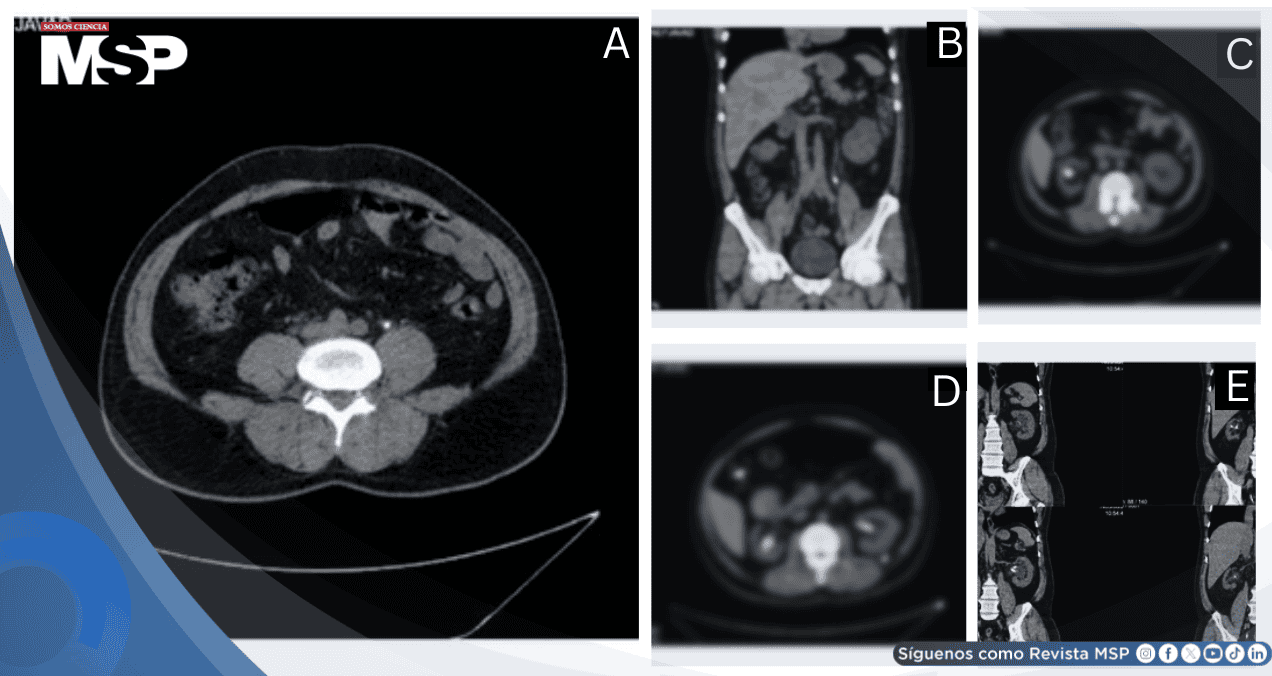

(A- D) Vista endoscópica que muestra el stent doble J anudado dentro de la pelvis renal izquierda. La imagen muestra el complejo entrelazamiento del stent, destacando los desafíos encontrados durante la intervención endoscópica para la extracción del stent.

Bajo anestesia espinal, se intentó extracción cistoscópica del stent DJ izquierdo con pinza, sin éxito. Mediante ureteroscopio semirrígido de 8 Fr, se identificó:

Incrustación significativa a lo largo de todo el stent DJ

Anudamiento de la punta superior del stent en pelvis renal izquierda

A pesar de que la tomografía computarizada preoperatoria no reveló la incrustación, probablemente debido a la sensibilidad limitada de la TC sin contraste para materiales radiolúcidos y la orientación del stent, la evaluación endoscópica confirmó su presencia.